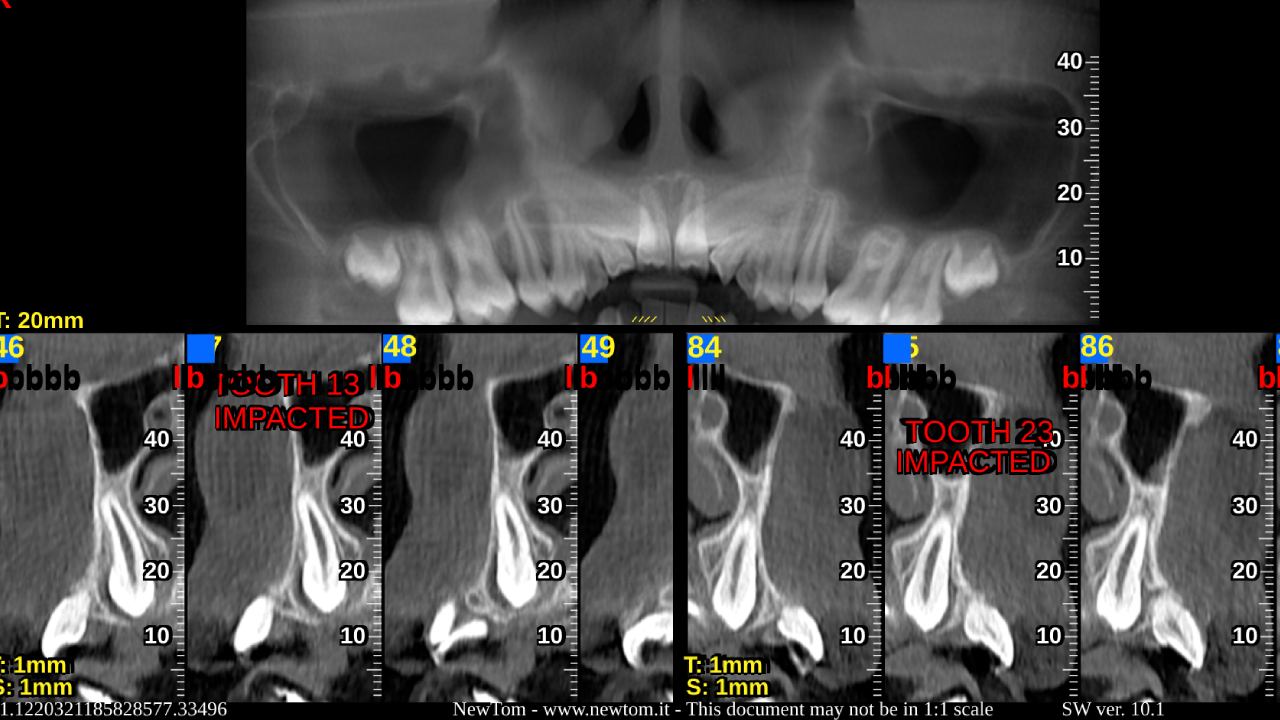

CBCT is a specialized type of CT scan designed for dental and maxillofacial imaging. It uses a cone-shaped X-ray beam to produce high-resolution 3D images, allowing for precise assessment of bone structures, tooth orientation, and soft tissues. This technology is particularly beneficial for complex cases where conventional 2D X-rays may not provide sufficient information.

CBCT is an advanced imaging technique that provides detailed 3D images of the dental and craniofacial structures. Unlike traditional X-rays, CBCT captures volumetric data, offering a comprehensive view of the teeth, jaws, and surrounding anatomy.

During a CBCT scan, the patient is positioned in the scanner, and the machine rotates around the head, capturing multiple images from different angles. These images are then reconstructed into a 3D model, allowing for comprehensive analysis of the dental and craniofacial structures.